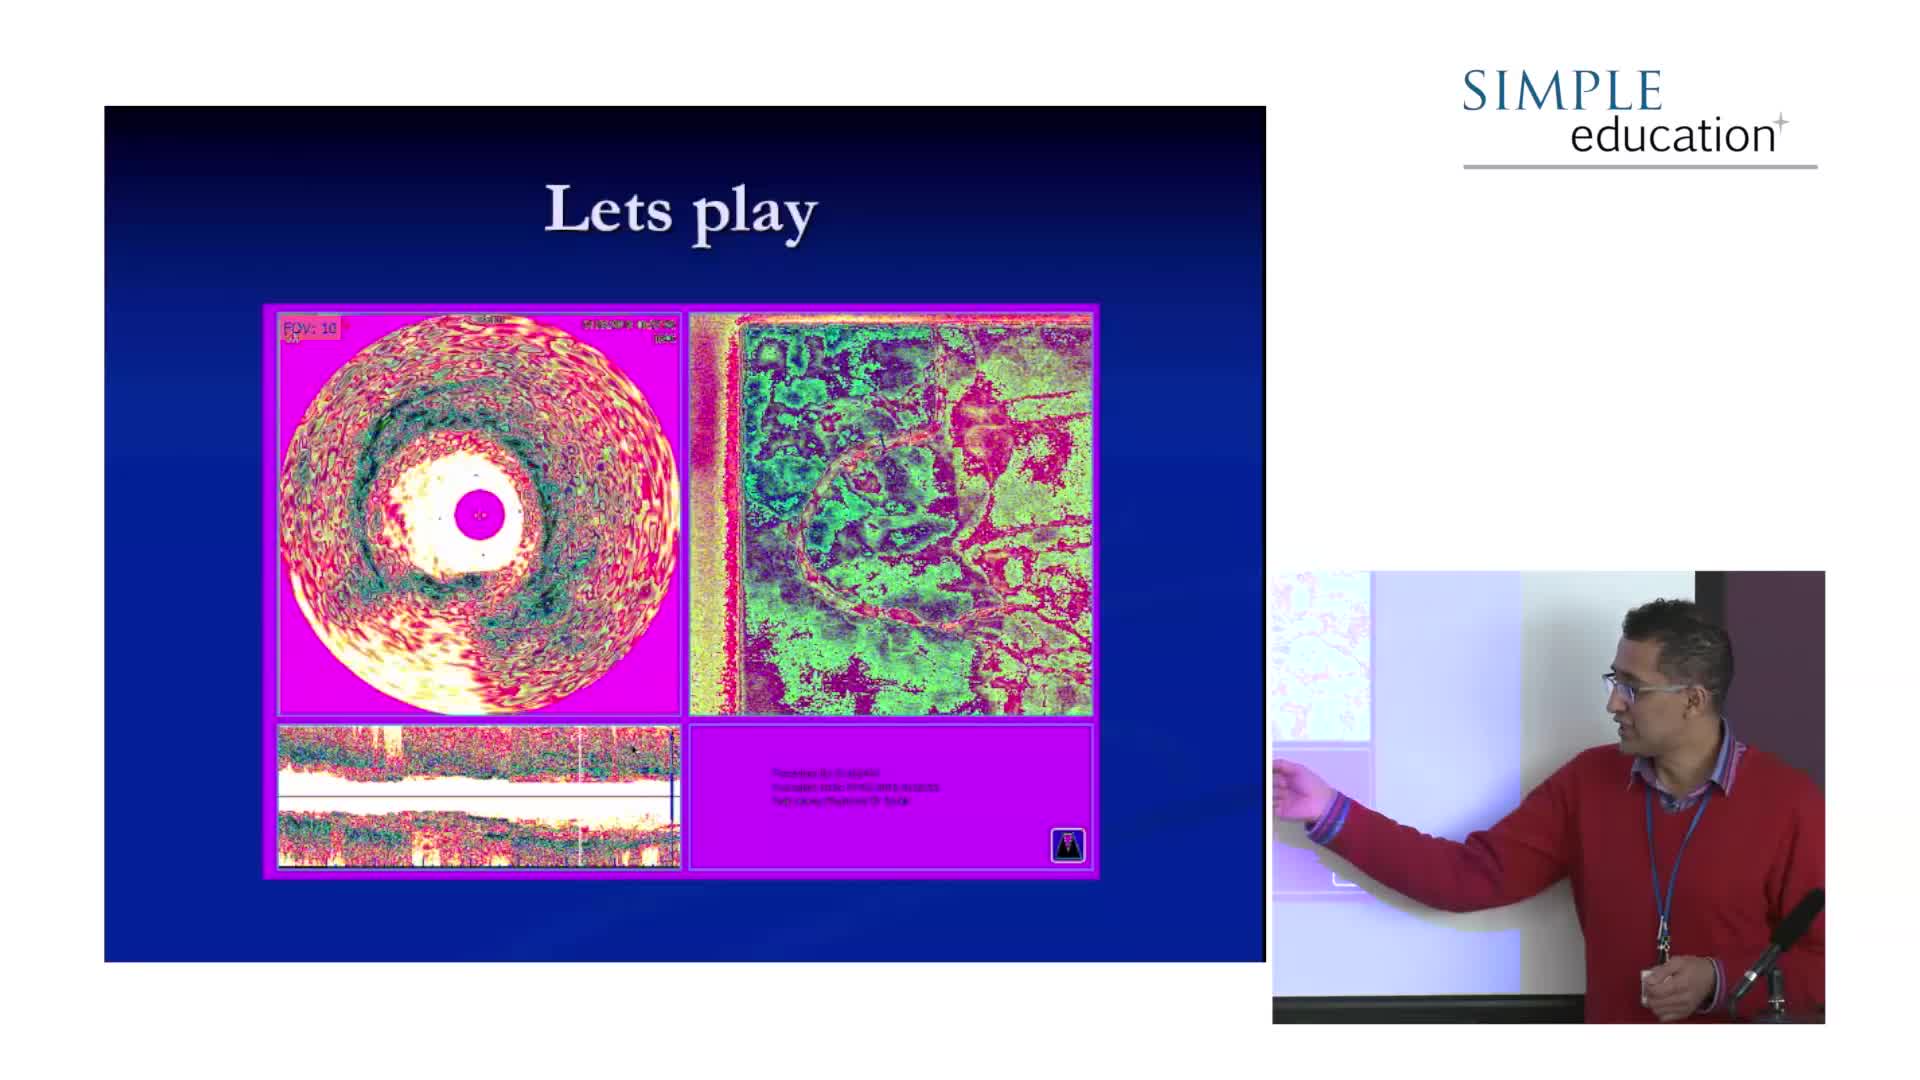

How to perform good co-registration measurements using iFR and IVUS - Prof Carlo Di Mario

Using SyncVision Co-registration to distinguish between focal and diffuse coronary disease. - Prof Giuseppe Tarantini

Essential Guide to Intra-coronary Imaging for the General Cardiologist - Dr. Iqbal Malik